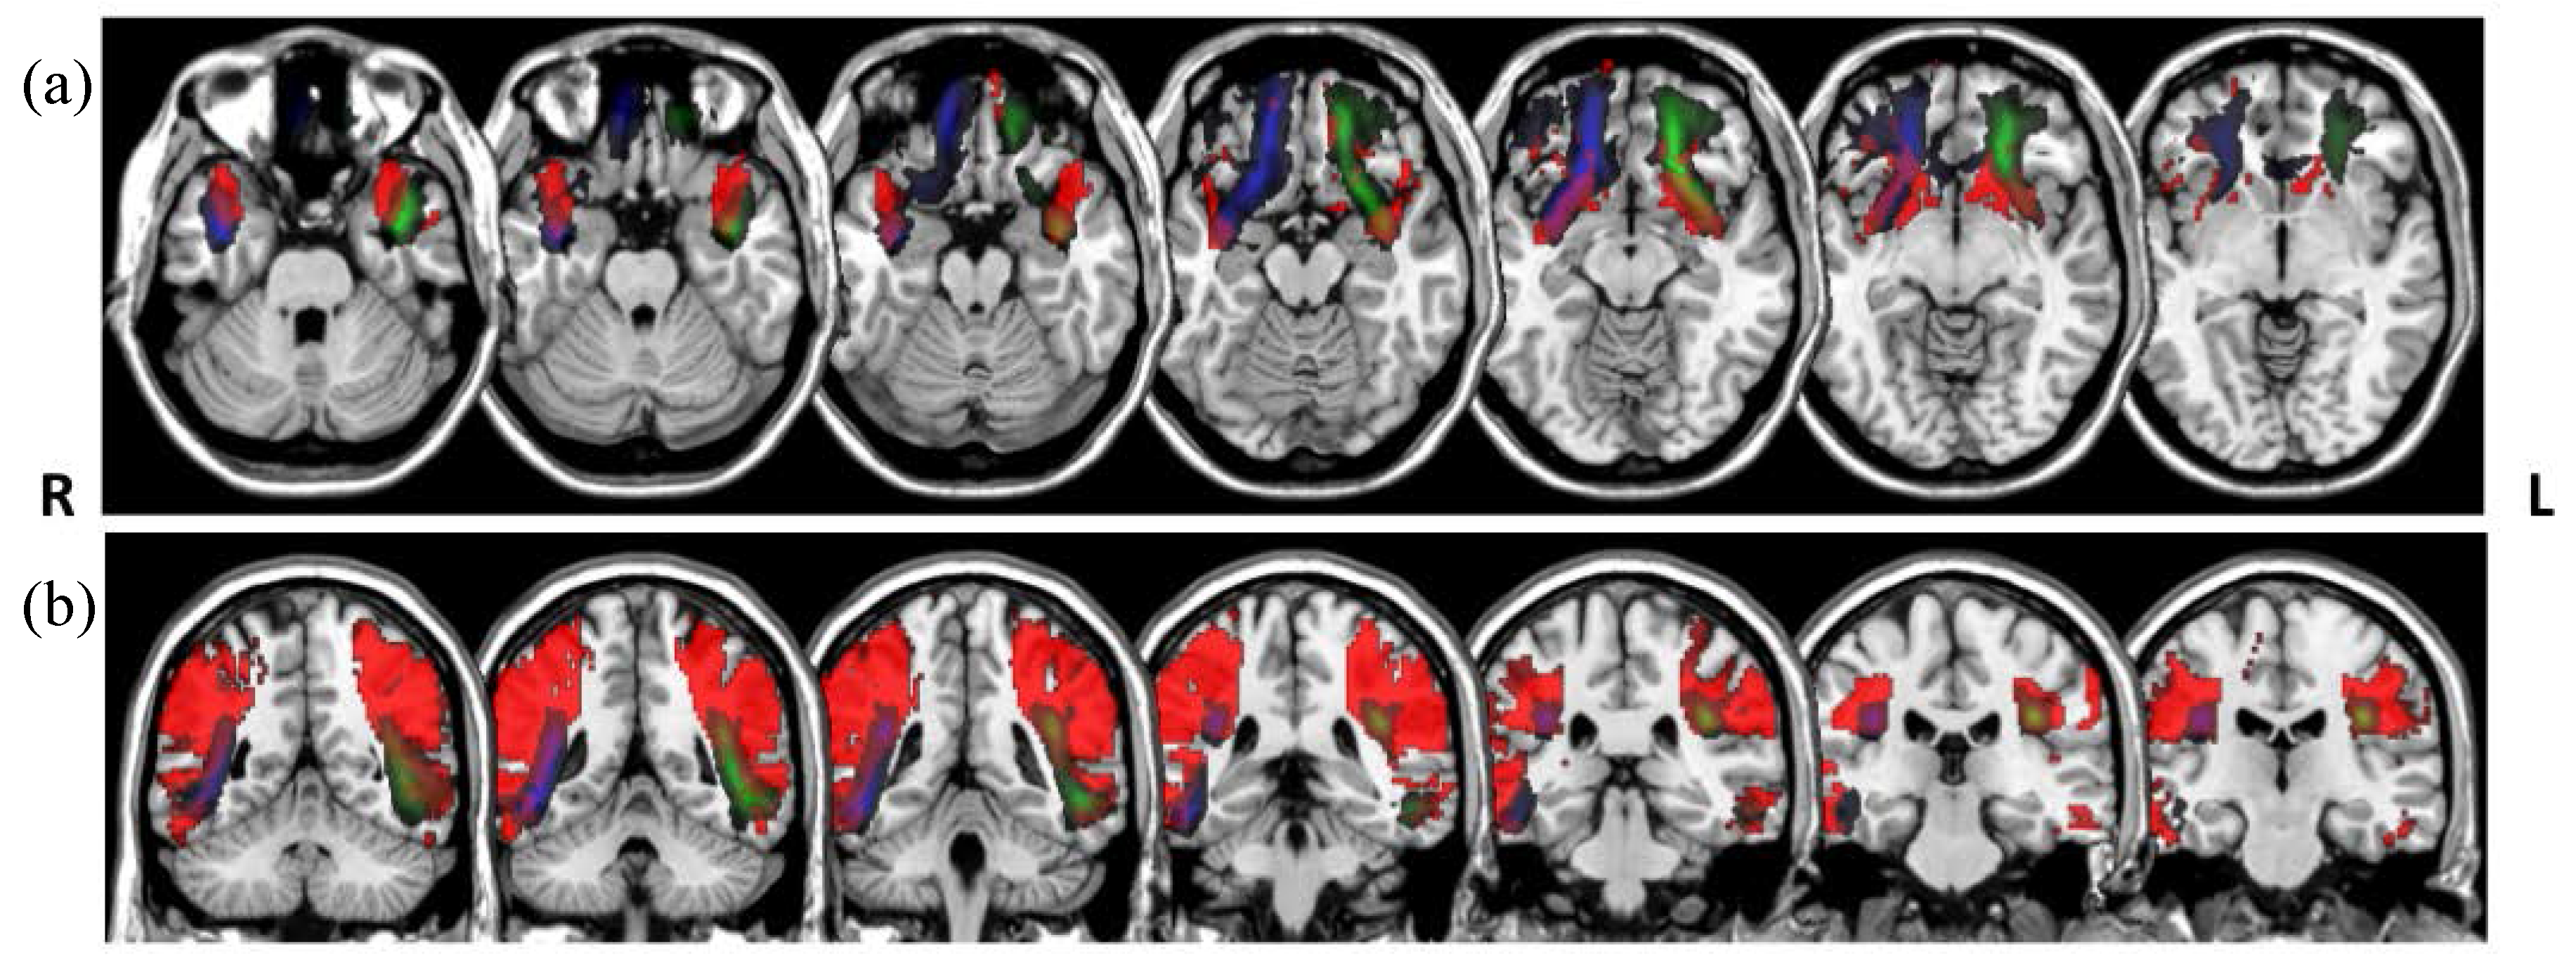

3.2. Assessment of Synthetic Tracts Sampled from PNT Models

We sampled the PNT models for the three different combinations of dataset and reference tracts. Figure 6 shows streamline representations of the synthetic tracts that were obtained. We can observe differences in the models trained in each case. The models that were generated from the atlas-based reference tracts reflect the shorter length of the references, particularly for the genu, Arc, and ventral cingulum. The dispersion of the streamlines in each case represents the degree of variability around the reference permitted by the model.

Figure 6.

Streamline representations of the synthetic tracts obtained by sampling from the PNT models generated from the training and LBC1936 data. First column: PNT model from the training dataset using the data-based reference tract; second column: PNT model from the LBC1936 dataset using the data-based reference tract; third column: PNT model from the LBC1936 dataset and the atlas-based reference tract. (a) genu (b) splenium, (c) Arc, (d) ATR, (e) Cing, (f) Cing, ventral, (g) ILF, (h) Unc, and (i) CST.

To assess that the PNT models themselves provided a good representation of the variability of each tract of interest, we sampled from the models to create the synthetic tracts shown in Figure 6. These are an illustration of the models as such, and demonstrate the relative merits of the different models, independently of any particular dataset. These tracts show, however, the influence of the originating reference tract on the models, as can be seen from the longer genu, Arc, and ventral cingulum sampled from the PNT models generated from the new data-based reference tracts. The models can therefore tell us a priori whether they epitomize plausible tracts; for example, if the sampled synthetic tracts are too short, or spread out too much, then the reference tract for a model may be misleading or less informative.